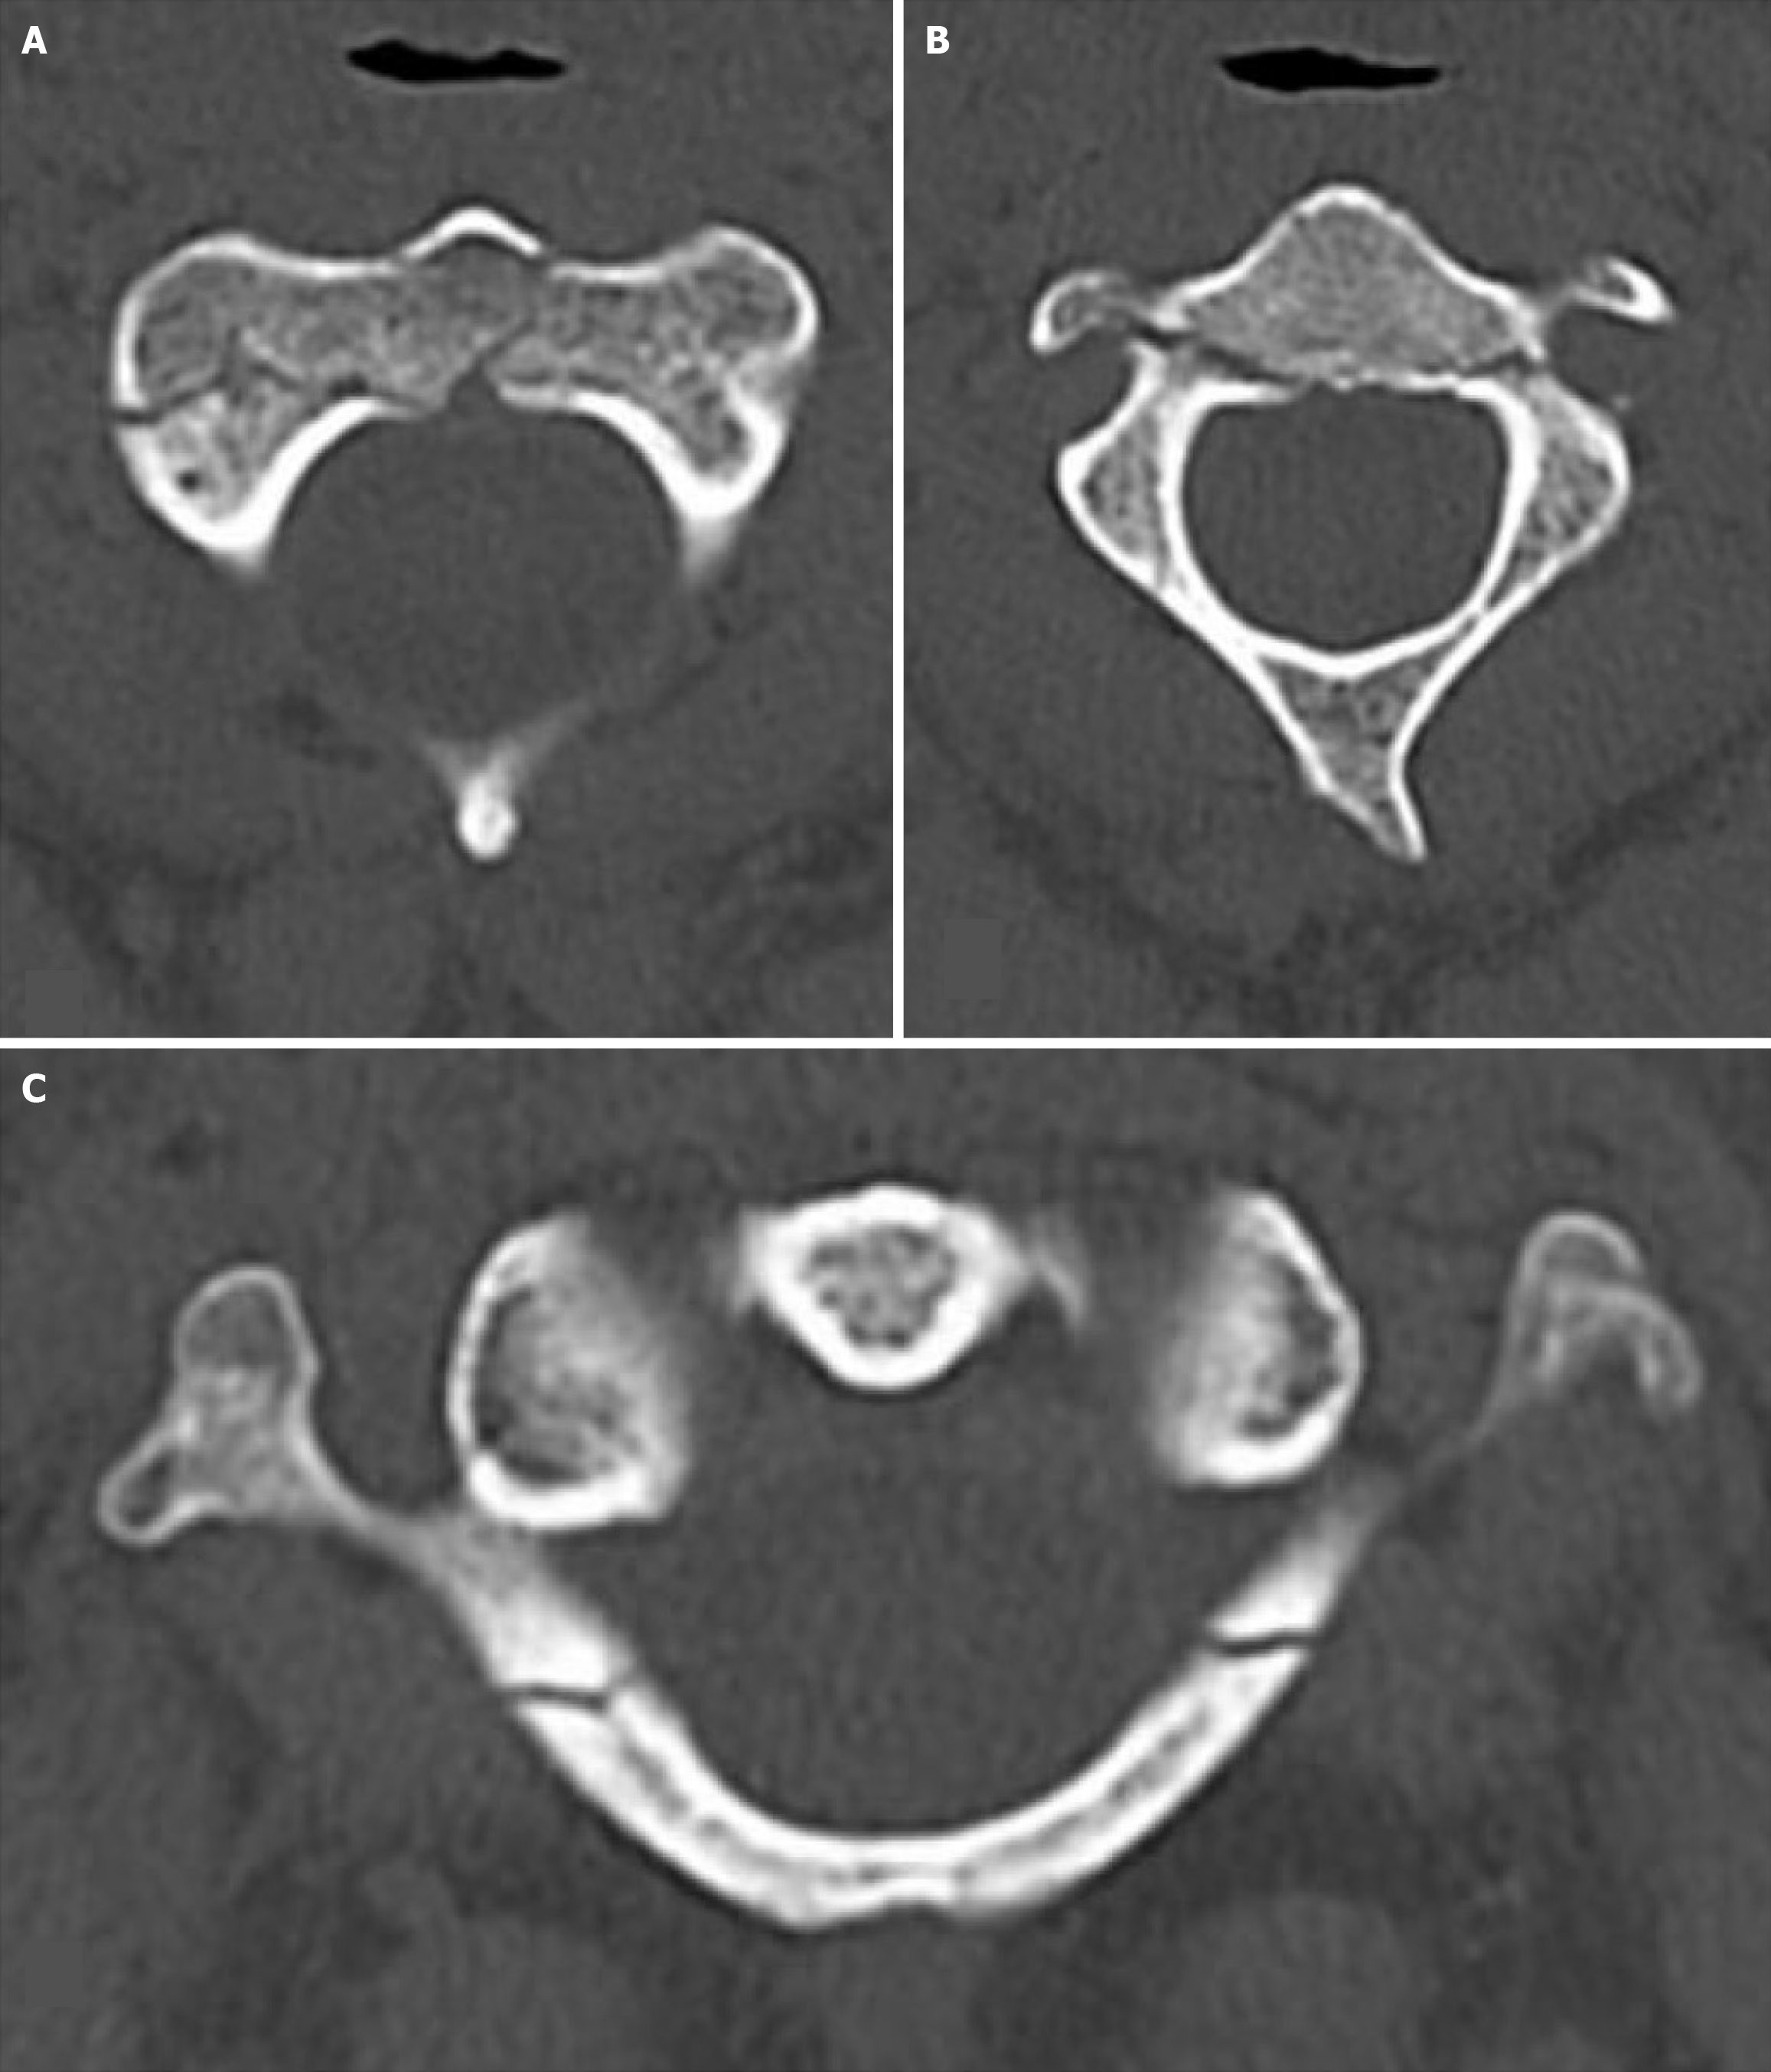

Case 1: Chest and pelvic X-rays were normal, and the Extended-Focused Assessment with Sonography for Trauma (e-FAST) examination was negative. Motor strength and sensation were intact in all four limbs. Pan-computed tomography (CT) revealed a fracture at the base of the odontoid process of the axis (C2) vertebra, with extension into the vertebral body (type III) and right lateral mass (Figure 1). Cervical spine magnetic resonance imaging (MRI) showed intact spinal ligaments and no spinal cord injury. Magnetic resonance angiography demonstrated normal opacification of bilateral vertebral arteries without dissection or aneurysm. This type III odontoid fracture likely resulted from combined flexion and axial loading, a mechanism common in unrestrained drivers during rollovers.

Odontoid process fracture: The odontoid process fracture is one of the most common fractures of the cervical spine and accounts for about 10% of all cervical spine injuries[13]. Both extension and flexion forces can cause this fracture. When the flexion/shear force is the cause of an odontoid fracture, there is anterior displacement of C1 on C2. The forward flexion of the cervical spine transmits shear forces to the base of the odontoid process, while axial load contributes to extension into the vertebral body and lateral mass. This type of injury pattern reflects the vulnerability of the craniovertebral junction to high-speed rollover trauma. The absence of ligamentous or vascular injury explains the patient’s stability and favorable prognosis with conservative management.

These injuries are usually asymptomatic unless they cause compression of the spinal cord. Odontoid process fractures are classified into three types, and management depends on the fracture level. A type 1 fracture of the odontoid process occurs at its tip and is usually managed nonoperatively. Type 2 fracture occurs at the base of the odontoid process. This type has a high rate of nonunion due to compromise in vascularity after fracture. These fractures are managed surgically, with either a halo or a C1-C2 fusion. In type 3, the fracture extends through the body of the atlas. These can be managed conservatively[13]. If there is injury to the surrounding ligaments along with the fracture on MRI, it indicates an unstable C1-C2 complex and necessitates surgery. In our series, one patient (case two) had a fracture at the base of the dens (odontoid process) with extension into the vertebral body and the right lateral mass (Figure 1). He was successfully managed conservatively.